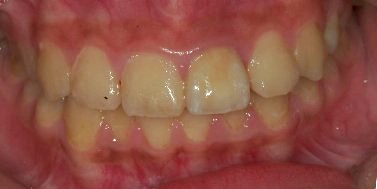

患者王小姐因左上正前牙疼痛劇烈前來求診 , 詳細問診之後, 了解該患者因多年前外傷造成前牙斷裂(見圖一) , 因當時只做緊急處理暫時用複合樹脂補起來 , 並未完整徹底根管治療 , 照數位X光(見圖二)後,發現左上正中門齒有根尖發炎的現象 , 初步診斷為慢性牙髓炎合併根尖骨質破壞 .

圖一 |